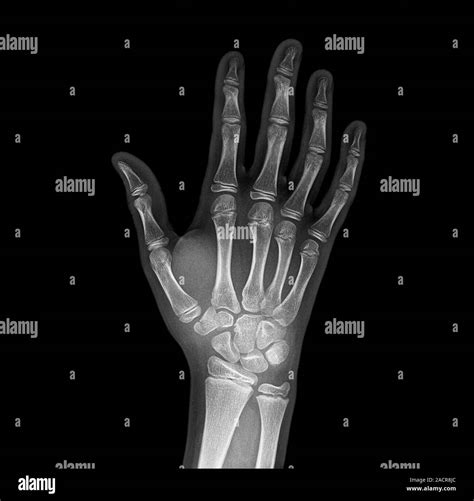

Understanding the intricacies of the human wrist is crucial for diagnosing and treating various conditions that affect this complex joint. One of the most effective diagnostic tools for evaluating wrist injuries and conditions is the Wrist Bones Xray. This imaging technique provides detailed views of the bones and joints in the wrist, helping healthcare professionals make accurate diagnoses and develop effective treatment plans.

A Wrist Bones Xray is a valuable diagnostic tool for evaluating various conditions and injuries affecting the wrist. This imaging technique uses X-rays to produce detailed images of the bones and joints, allowing healthcare professionals to identify fractures, dislocations, and other abnormalities. Some of the key benefits of a Wrist Bones Xray include: